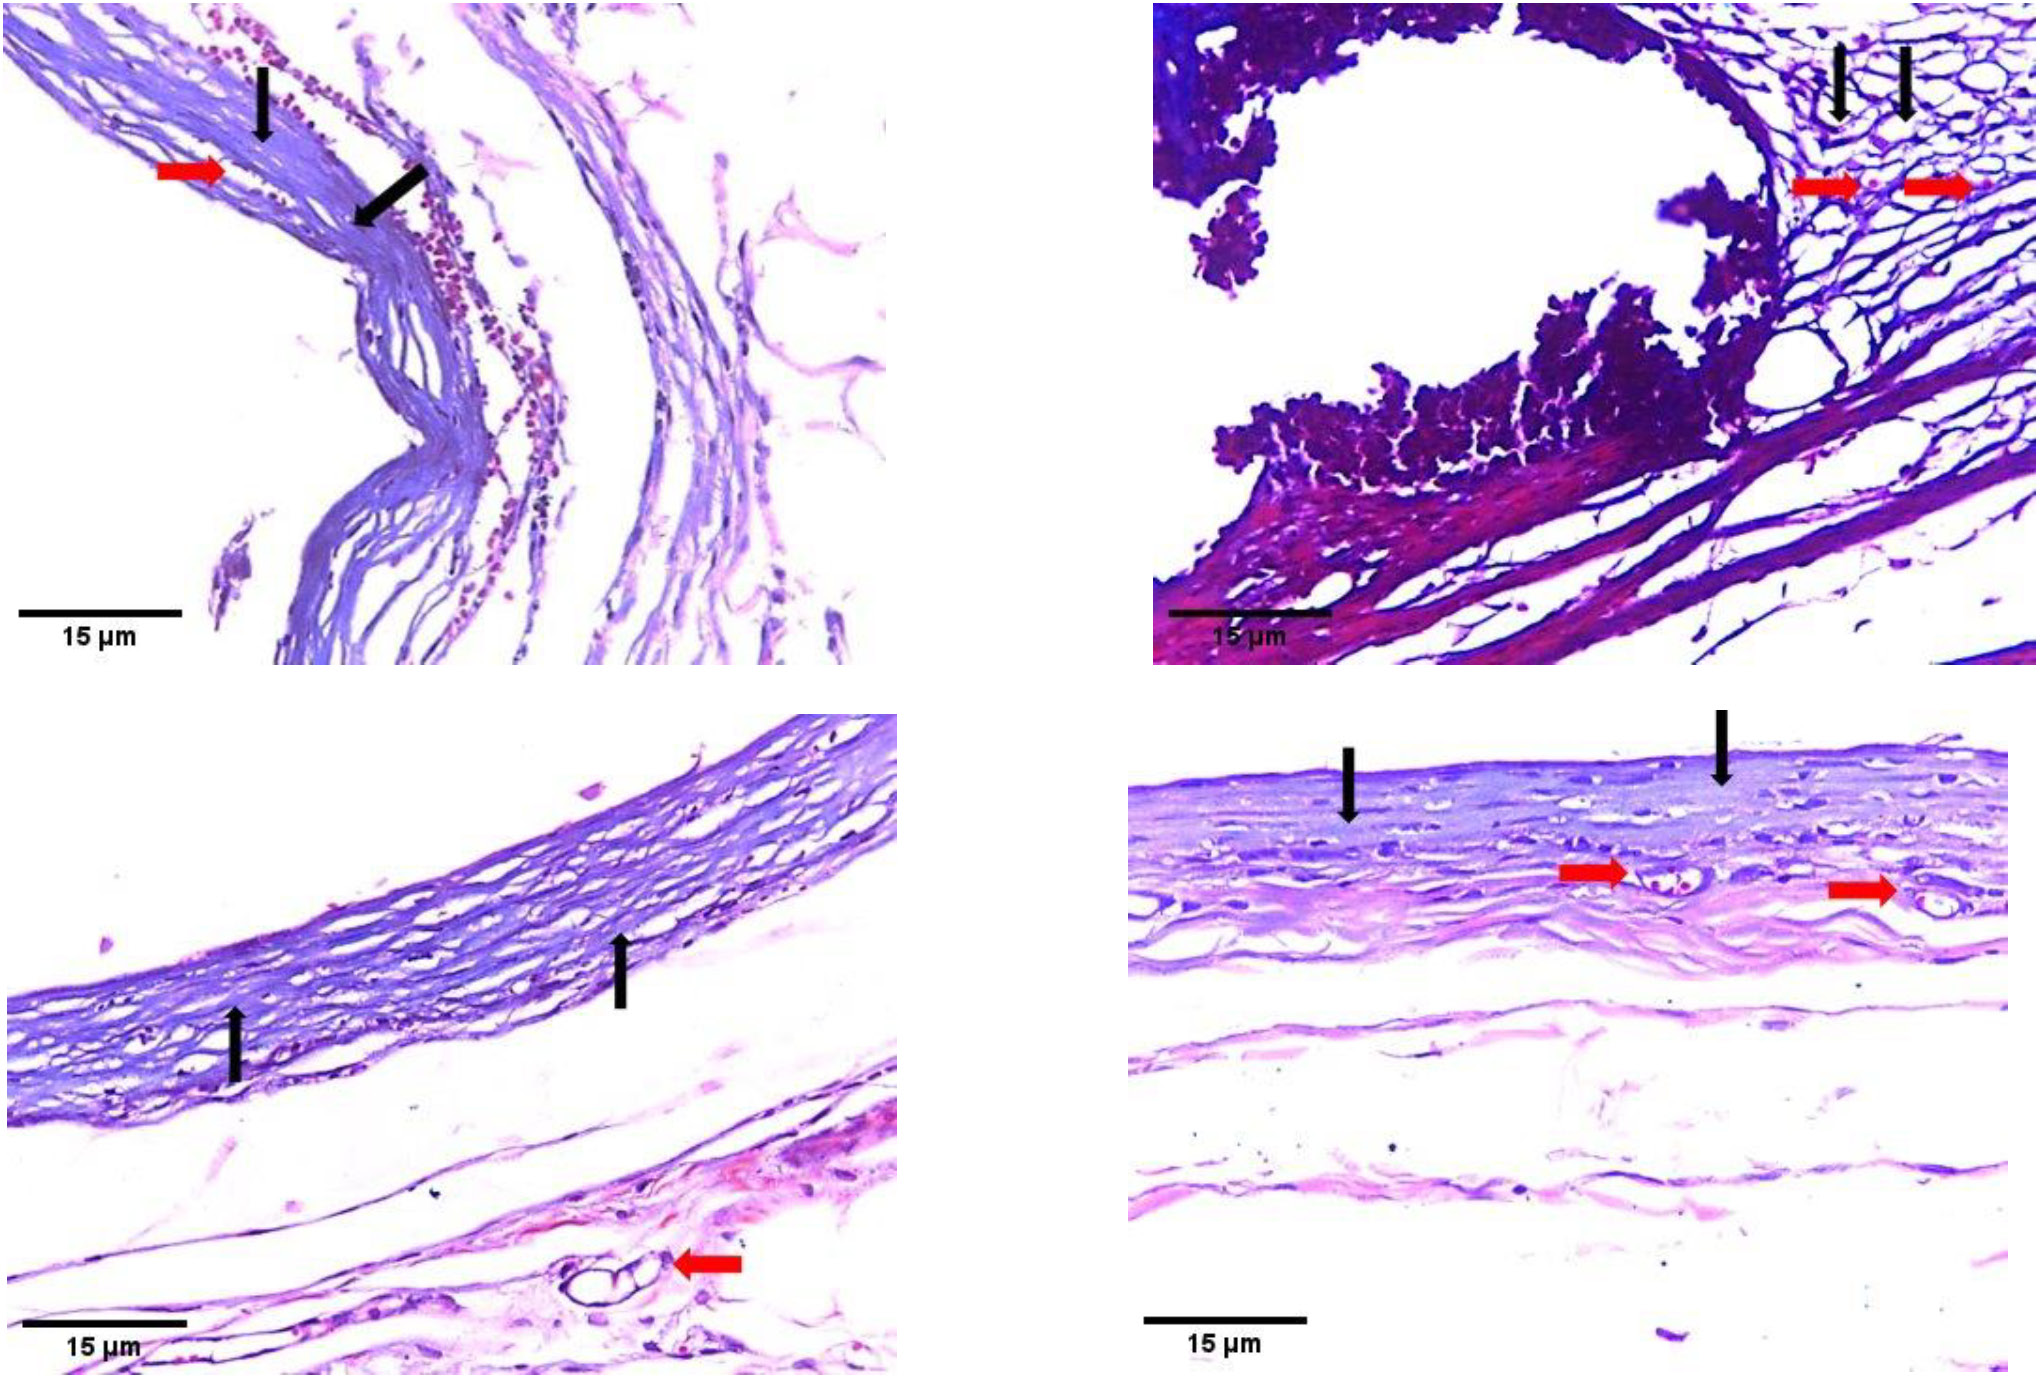

MT staining:

MTA subgroup 2 (Figure 4A) and TheraCal LC subgroup 2 (Figure 4B) revealed several fibroblasts within a band of dense collagen fibers, which stained lighter with trichrome as compared to the collagen fibers observed in mature granulation tissue. Fibroblasts and blood vessels were also present, and inflammatory cells, mainly lymphocytes, were evident. TheraCal PT subgroup 2 (Figure 4C) and the control subgroup 2 (Figure 4D) showed deposition of regularly arranged collagen fibers, along with evidence of newly formed blood vessels.